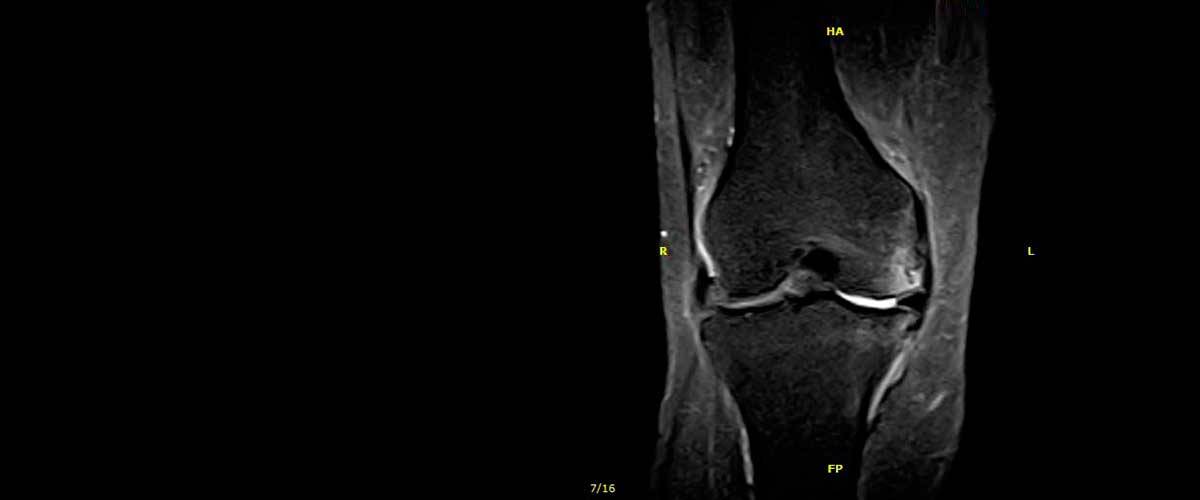

Contamos con equipos de resonancia magnética musculo-esquelética capaces de realizar exámenes con descarga de peso o bipedestación.

En nuestros centros se realizan estudios y diagnósticos de resonancia magnética musculo-esquelética

de Resonancia ,Magnética Musculo-Esquelética, de la marca italiana Esaote, es único en su diseño ya que nos permite realizar exámenes en bipedestación (el paciente estará de pie, para que se tenga otra perspectiva del comportamiento del cuerpo durante el examen).